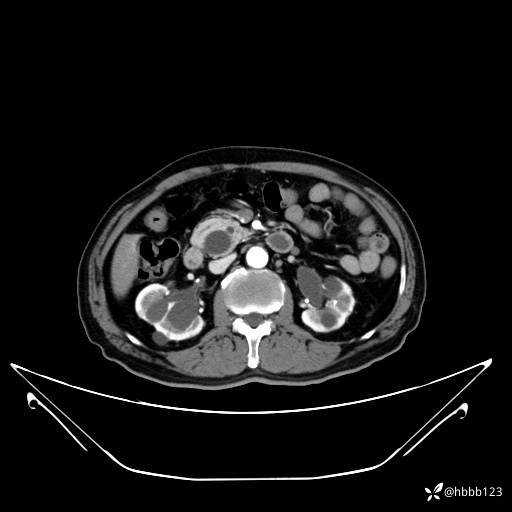

门脉期: